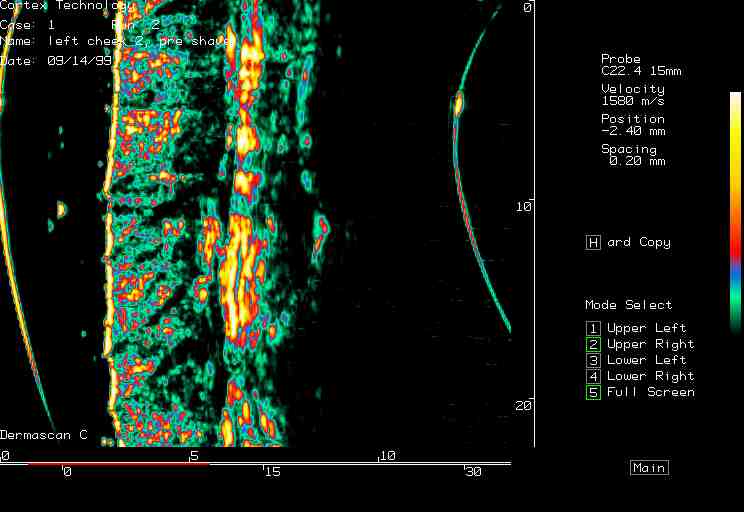

| Shaving reactions |  Cheek, prior to shaving |

Cheek, 0 min post shaving |

Cheek, 90 min post shaving |